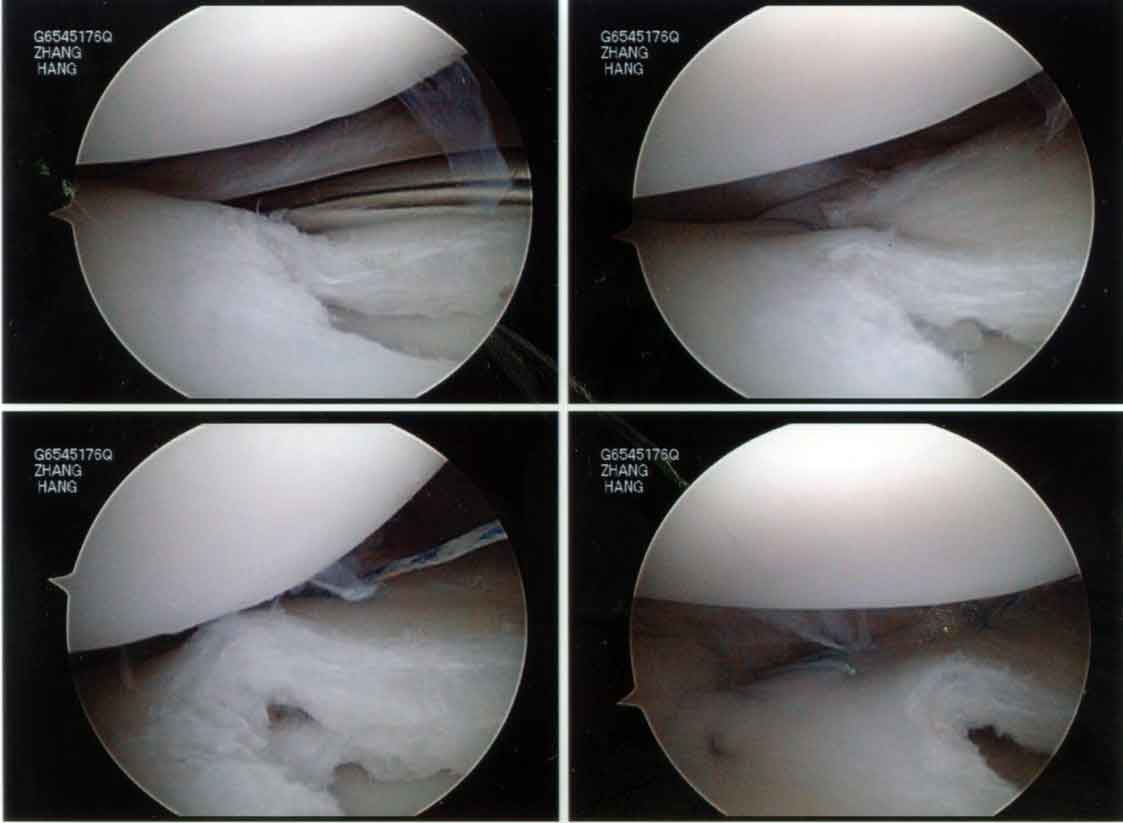

Next, the torn part of the meniscus was repaired to the capsule using a combination of all-inside and inside-out meniscus repair technique.

I will probably talk more about these meniscus repair techniques in a later article.

The final reconstructed discoid lateral meniscus looked like this: